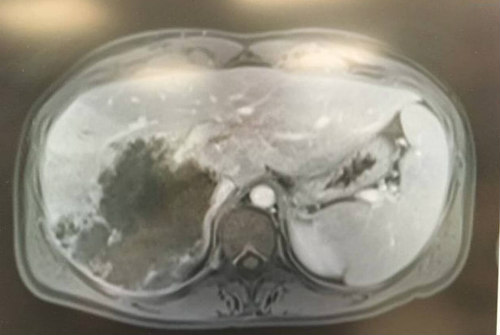

Ο πόνος έφτανε μέχρι τα πλευρά της και τότε οι γιατροί εντόπισαν μια σκιά.

Αμέσως την ενημέρωσαν πως ήταν καρκίνωμα και μάλιστα σπάνιας μορφής, ο οποίος εμφανίζεται σε άτομα κάτω των 40 ετών.

Λίγο πριν ξεκινήσουν οι χημειοθεραπείες, έκανε συμπληρωματικές εξετάσεις που αποκάλυψαν την φρικτή, αλλά όχι θανατηφόρα ασθένεια.

Δείτε στις πιο κάτω φωτογραφίες τι υπήρχε στο συκώτι της: